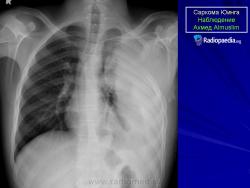

С Радиопедии.

Саркома Юинга грудной стенки.